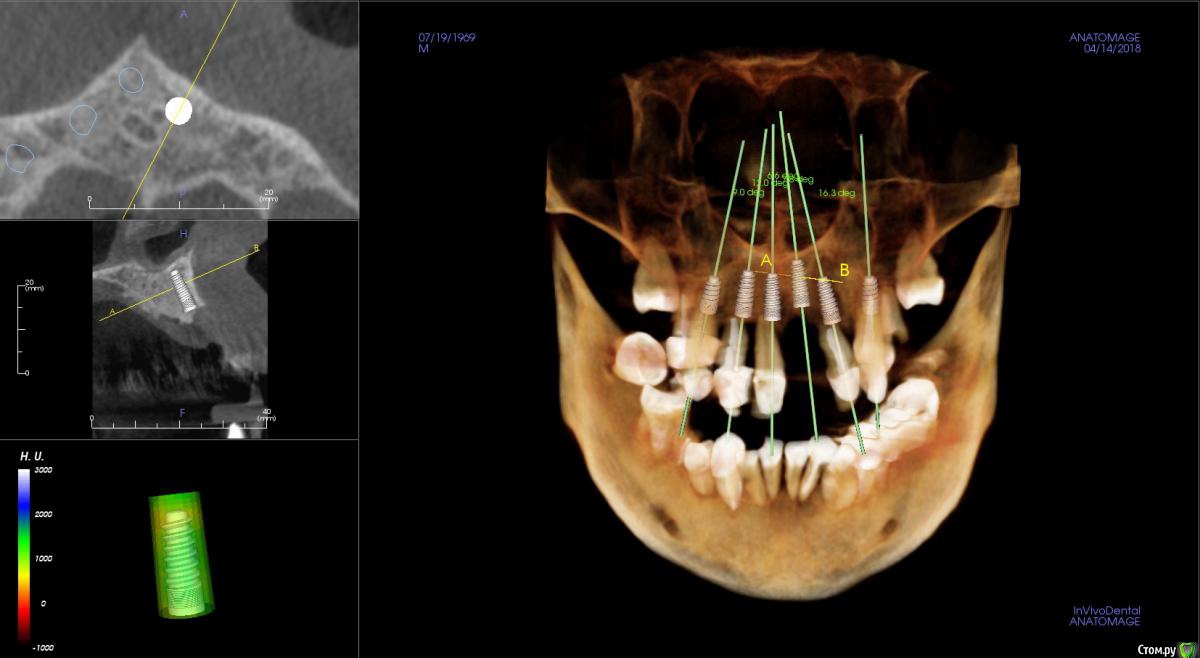

JurJul Опубликовано 17 апреля, 2018 Поделиться Опубликовано 17 апреля, 2018 Не знаю, возможно мой случай в раздел протезирования и не подходит, возможно нужна хирургия и имплантация. История. Живу в Белоруссии. В 2000 году сделал всё, что нужно было: мосты, коронки, виниры на передние зубы. На то время по высокому уровню стоматологии. Где-то через 2 года обнаружили онкологию (семенома) на 1 стадии. Операция, химия, лучевая. Препараты на химиотерапии этопозид, цисплатин. Всё благополучно прошло. Потом где-то через 2-3 года мосты и коронки стали беспокоить и постепенно они снялись. В начале 10-х годов был на нескольких консультациях - сказали, что у меня 2 варианта: ждать пока само всё выпадет и потом ставить всё полностью съемное "под Карегу" и второй вариант - удалять всё раньше и опять же ставить полностью под Карегу. Я как-то не могу с этим смириться, всё же думаю, что возможны варианты ещё, тем более, что научно-технический как и медицина со своими технологиями двигаются семимильными шагами. Про импланты мне говорили, что в моём случае ничего не будет стоять, т.к. была в прошлом химия и лучевая и у меня всё подвижно, что собственно подтверждается состоянием зубов и корней, которые норовят выходить сами. Были частые воспаления дёсен и признаки пародонтоза. В последние месяцы стали шататься передние верхние, прямо похоже как у детей, когда зубы меняются... И вот совсем недавно выпал (помог ему немного) верхний 1-ца. Бисфосфонаты не принимал. Зубы после онко удалял. Лунки заживали нормально.В субботу 14.04 был на консультации у имплантолога. Ведущий специалист в этой области в РБ... во всяком случае так его позиционирует Гугл )) Так вот мне сразу был предложен самый оптимальный в моём случае вариант - всё на 6 на обе челюсти и всё сразу и быстро. Удаляем всё и сразу и тут же вкручиваем импланты (Израиль или Нобель). Через 5-7 дней ставим временный несъемный протез и через полгода вуаля постоянный несъемный (либо керамику либо цирконий по желанию). Типа это в моём случае самое оптимальное и не очень тяжёлое в физическом и психологическом плане (сразу с зубами, не нужно съёмный протез полгода носить или без зубов долго ходить )... Я, честно говоря, не готов на такой вариант... Я понимаю, что возможно хороших зубов, которые смогут служить опорой под мост/ы, может и нет. И, возможно, и нужно будет всё удалить... Но я думаю, может и ошибаюсь, что есть и др. методы имплантации, если это неизбежно. Как мне сказали на консультации, что предложенный вариант единственный для верхней челюсти, варианты могут быть по низу, но по верху - без вариантов...Озвучена по стоимости работа "под ключ" : с израильскими имплантами 12 тыс. дол. , с американскими 20 тыс. дол. Дело даже не в стоимости. Просто мне не хотелось бы стать одним из авторов стом. форумов с мольбой о помощи в исправлении чьей-то работы с имеющимися проблемами. Больше всего на свете я не хочу проблем и переделок. Я понимаю, что на 100% нельзя быть уверенным в результате, но минимизировать риски, выбрав самый лучший или оптимальный вариант, можно. Вот поэтому я решил обратиться сюда за консультацией. Ссылка на 3D томографию: https://drive.google.com/open?id=1puDkkPZG_C-UQCklhUjX5sdAS_SOIooZВзываю к помощи товарищей врачей! Только на вас уповаю Ссылка на комментарий

St. Опубликовано 17 апреля, 2018 Поделиться Опубликовано 17 апреля, 2018 Обзорные срезы ( верх, низ, топография нижнечелюстного нерва), дефект в обл 21 Ссылка на комментарий